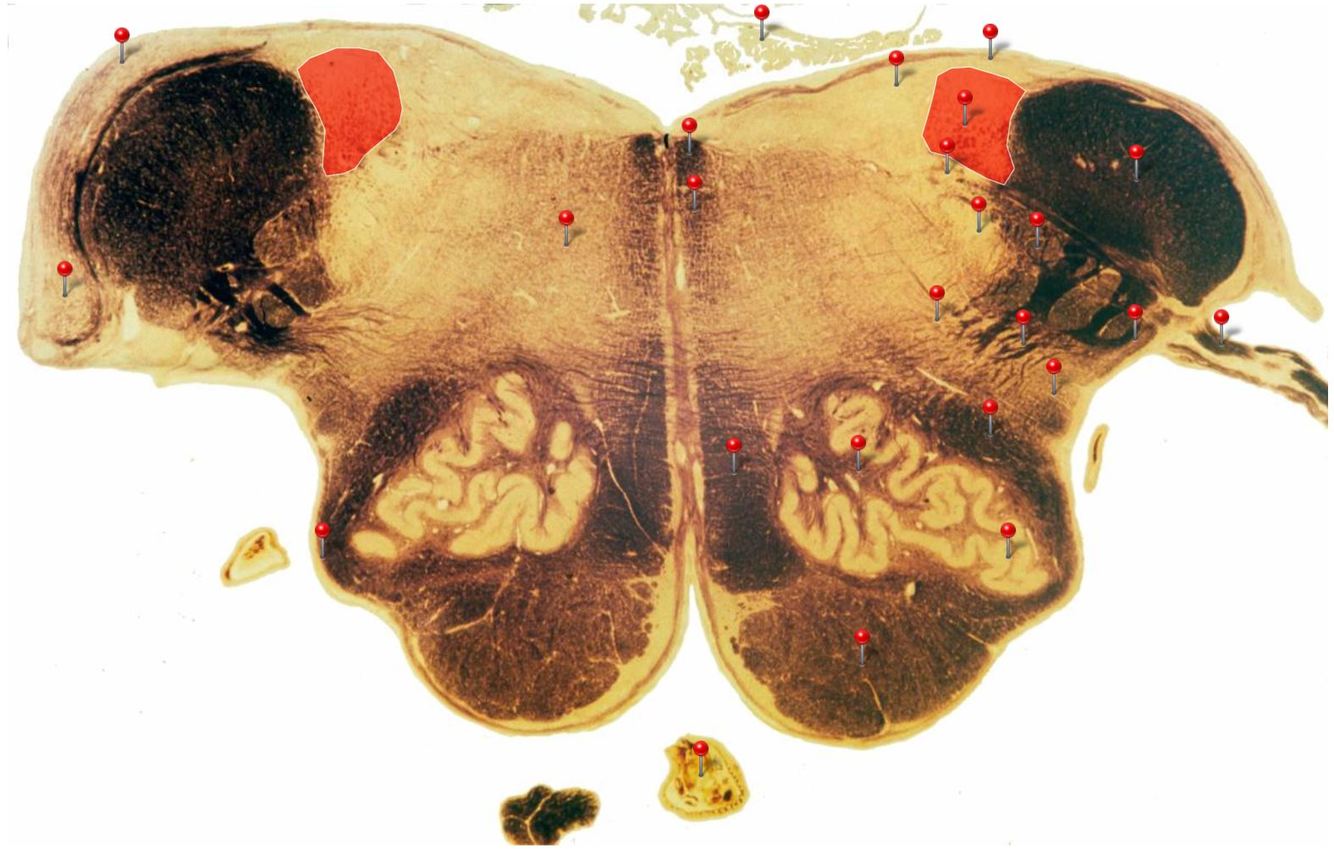

11

Q

Corticospinal Tract

Rostral Medulla

Controls precision and speed of skilled movements involving the distal muscles of the contralateral limbs, particularly those of the hands and fingers

12

Nucleus Ambiguus

Neurons supply the muscles of the pharynx, larynx, upper oesophagus and heart

13

Basilar Artery

Provides blood supply to much of the cerebellum, pons, midbrain and posterior thalamus as well as part of the temporal (inferior surface) and occipital (medial and inferior surfaces) lobes

14

Olives

Elevations formed by the inferior olivary nuclei which integrate information from a variety of sources before relaying it to the cerebellum

15

Rubrospinal Tract

Assists in the control of movements of the hands and fingers

16

Medial Vestibular Nucleus

Process inputs from vestibular receptors of the inner ear and are involved in the regulation of posture and the coordination of head and eye movements

17

Spinal Trigeminal Tract

Transmits somatosensory (crude touch, pain and temperature) inputs from the Trigeminal nerve (CN V) through the midpons and medulla to the spinal trigeminal nucleus.

18

Ventral Cochlear Nuclei

One of the relay nuclei for the auditory fibres of the vestibulocochlear nerve (CN VIII) and functions to modify inputs to the higher auditory structures

19

Medial Longitudinal Fasciculus

Pathway through which eye movements are coordinated with changes in head position

20

Dorsal Cochlear Nuclei

One of the relay nuclei for auditory fibres of the vestibulocochlear nerve (CN VIII) and functions to modify inputs to the higher auditory structures

21

Inferior Olivary Nucleus

Plays an important role in the learning of new motor skills

22

Solitary Nucleus

Processes visceral afferent (GVA and SVA [taste]) inputs from CN VII, IX and X and relays them to the reticular formation and visceral efferent nuclei

23

Spinal Trigeminal Nuclei

Processes sensory inputs, particularly pain and temperature, from the head and neck and relays them to the ventral posteromedial nucleus of the thalamus

24

Inferior Vestibular Nucleus

Plays a role in the maintenance of balance and the coordination of eye and head movements

25

Medial Lemniscus Rostral Medulla Transmits sensations of **discriminative touch, vibration, proprioception** an **stereognosis** from the *gracile* and *cuneate nuclei* to the *ventral posterior nuclei of the thalamus*

26

Ventral Spinocerebellar Tract Rostral Medulla Provides feedback to the cerebellum concerning motor activity (including reflexes) in the lumbosacral levels of the spinal cord

27

Glossopharyngeal Nerve (CN IX) Rostral Medulla Transmits taste and tactile sensation from the posterior part of the tongue, pharynx and ear, and visceral sensation from the chemo- and baroreceptors of the carotid body and sinus (also supplies efferent fibres to the otic ganglion and stylopharyngeus m.)

28

Inferior Cerebellar Peduncle Rostral Medulla Formed by pathways passing in both directions between the medulla and cerebellum

29

Tectospinal Tract Rostral Medulla Function in humans not precisely determined; thought to mediate reflex movements of head in response to visual and perhaps auditory stimuli

30

Olivocerebellar Tract Rostral Medulla Transmits information from inferior olivary nucleus to the *contralateral* cerebellum, where it forms the **climbing fibres**

31

Lateral Vestibular Nucleus Rostral Medulla Contains cell bodies of the (lateral) vestibulospinal tract which regulates the activity of **axial** and **proximal** limb muscles in order to **maintain balance and posture**